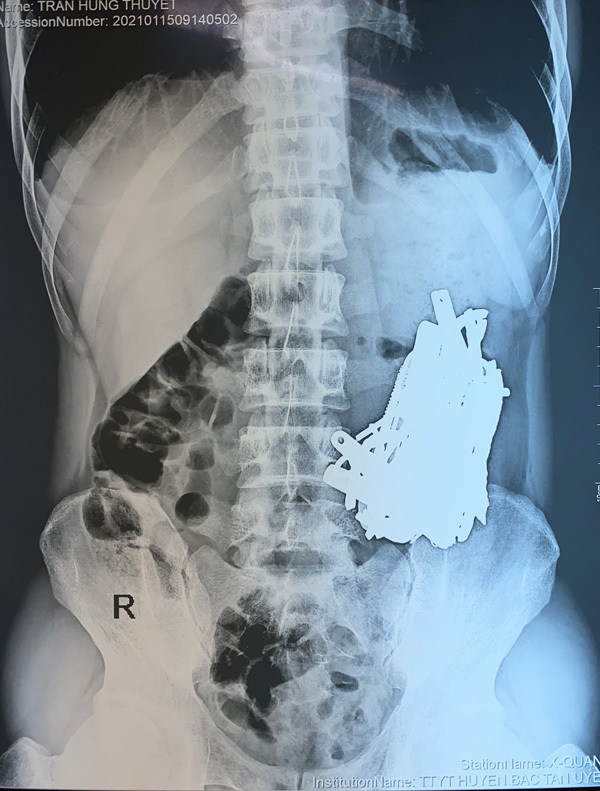

Phim chụp X-quang thấy rõ một chùm dị vật trong bụng bệnh nhân

Bác sĩ Dũng cho biết, do số lượng dị vật trong bụng bệnh nhân quá nhiều nên ê-kíp phải tiến hành mổ mở và chụp C-ARM (X-quang trong mổ) để tránh sót dị vật.

Trong quá trình phẫu thuật, bác sĩ phát hiện nhiều kim loại đã bị ăn mòn trong ổ bụng anh T. gồm đinh, thìa, bấm móng tay, lưỡi dao, thỏi sắt…